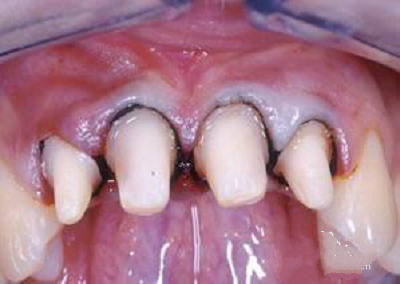

引起牙龈黑线的

这种也是佩戴烤瓷牙(镍铬合金、钴铬合金等)后最常出现的情况,因其价格低廉在当时备受欢迎,但是在长期的佩戴过程中会出现牙龈发黑的现象,这是因为非贵金属烤瓷牙在口腔内氧化成灰色氧化物,时间久了沉淀于牙龈,造成牙龈黑线,若不及时拆除,很可能会出现牙龈炎、牙周炎甚至牙齿脱落。